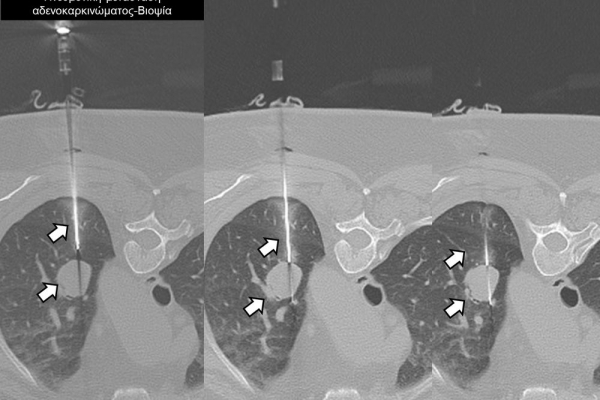

Η διαδερμική βιοψία είναι μία ελάχιστα επεμβατική μέθοδος λήψης υλικού από τον όγκο για κυτταρολογική και ιστολογική εξέταση, από εστιακές αλλοιώσεις του ήπατος, πνεύμονα, νεφρού κλπ. Συστήνεται από τον κλινικό ιατρό ανάλογα με το είδος και το μέγεθος της βλάβης και πραγματοποιείται με ασφάλεια από επεμβατικό ακτινολόγο με την καθοδήγηση αξονικού τομογράφου ή υπερήχων. Στη σύγχρονη ογκολογική θεραπεία όπου γίνεται προσπάθεια καταπολέμησης του καρκίνου σε μοριακό επίπεδο κρίνεται αναγκαία η ακριβής ιστολογική ταυτοποίηση του όγκου ώστε να εφαρμοσθεί εξατομικευμένη θεραπεία για το βέλτιστο αποτέλεσμα. Οι κατευθυνόμενες βιοψίες στοχευουν στο να παρέχουν στον κλινικό ογκολόγο το απαραίτο ιστοπαθολογικό υλικό που θα του επιτρέψει να εφαρμόσει την κατάλληλη θεραπεία για τον ογκολογικό ασθενή.